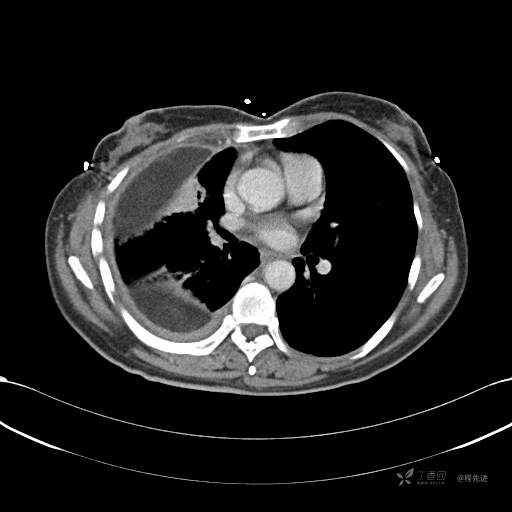

患者性别:女

患者年龄:51岁

简要病史:胸闷半年